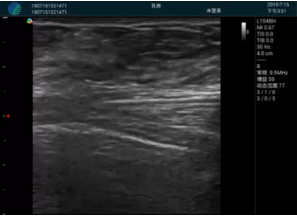

M20查看:囊內回聲均勻,邊界清晰,囊壁光滑

M20引導抽吸術后囊腫消失,原區(qū)域空腔形成,脂肪層與腺體層架構發(fā)生改變